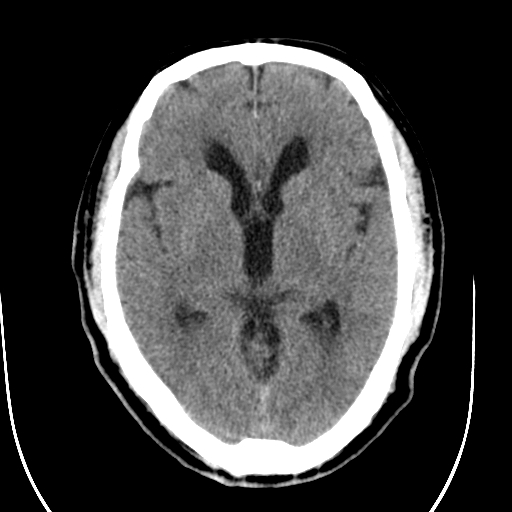

标题: CT28335:男,58岁,请各位看看是不是有脑积水,蝶窦内高密 [打印本页]

标题: CT28335:男,58岁,请各位看看是不是有脑积水,蝶窦内高密

轻度积水,蝶窦正常。

脑积水!建议行mri!

1)脑积水。2)副鼻窦炎。